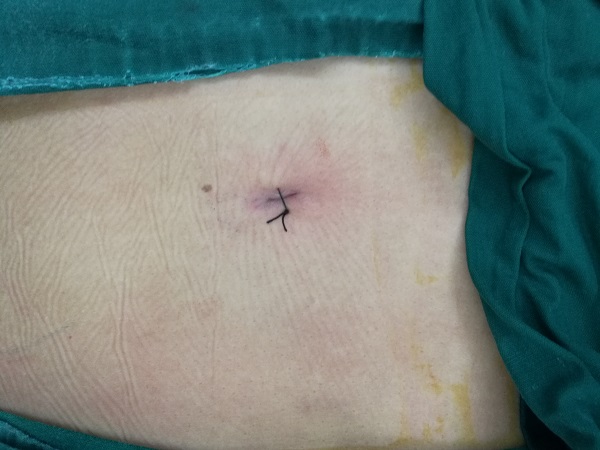

對(duì)于腰椎間盤突出癥,傳統(tǒng)的開放性切除手術(shù),創(chuàng)傷大、恢復(fù)慢,不利于患者的預(yù)后。椎間孔鏡技術(shù),則在手術(shù)室局麻下行微創(chuàng)切除腰椎間盤突出,術(shù)前不需過多的準(zhǔn)備及要求,術(shù)中手術(shù)切口只有1cm左右,術(shù)后即可解除神經(jīng)的壓迫,患者疼痛隨即消失下地行走,不用留置任何管道,立刻恢復(fù)正常生活。只需一個(gè)小孔,一個(gè)透視點(diǎn),即可完成腰椎椎間盤突出部分的切除,大大減輕患者的痛苦,縮短住院時(shí)間,真正達(dá)到微創(chuàng)手術(shù)外科的理念。

手術(shù)切口僅1cm